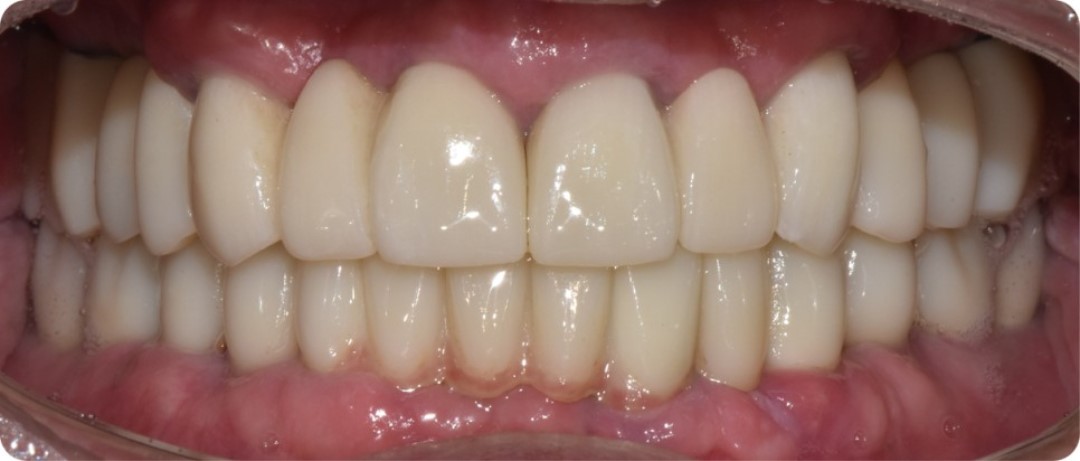

379b38bb634bc.jpg

임플란트 식립 개수를 늘려 강한 저작력을 견딜 수 있도록 설계

우리 환자분의 케이스도 잇몸뼈는 약한데 저작력이 강한 경우였기 때문에

임플란트 개수를 늘려서 강한 저작력을 견딜 수 있게 설계를 해준 것입니다.

하지만 여기서 주의할 것은, 임플란트 사이 간격이 충분해야 하는데요.

보통은 임플란트와 임플란트 사이 간격이 3mm 정도는 되어야

임플란트가 뼈와 붙는데 무리가 없습니다.

앞서 말씀드렸던 것처럼, 김태수님은 잇몸뼈가 원래 많이 부실하셨던 데다가

저작력도 강한 편이어서 임플란트 직경이 두꺼운 걸로

위, 아래 각각 10개씩 임플란트를 심어 드렸는데요.

e92146487e92c.jpg

강한 저작력을 충분히 견딜 수 있을 정도로

튼튼한 기초공사를 해드렸기 때문에

구강 사진을 봐도 보철물이 상당히 자연스럽고

교합 또한 안정적으로 잘 설계된 모습입니다.